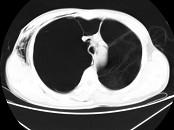

问题 男,32岁,被车撞伤后1小时,请结合影像图像选择其最可能的诊断为 ( )

选项 A.右侧气胸 B.右肺不张 C.右侧气胸并皮下纵隔气肿 D.右侧肺大疱并皮下纵隔气肿 E.支气管断裂

答案 C